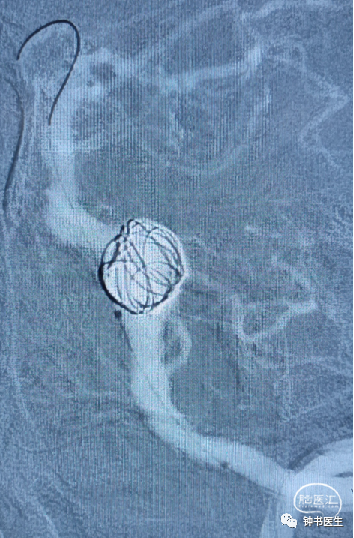

椎基底夹层动脉瘤:65Y M,脑干梗塞

术后患者无明显不适(TB 6.0X45)